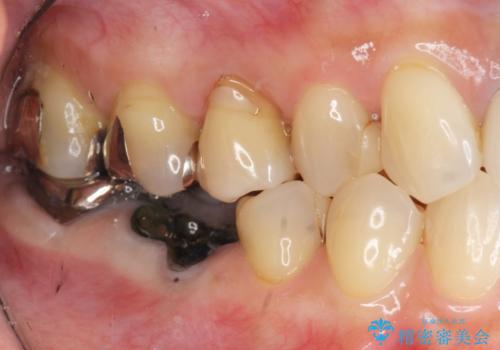

- 銀歯が取れてしまい、治療を希望され来院されました。

歯には大きな穴が開き、虫歯も大きくなってしまい残すことが難しいような状況であったため抜歯を余儀なくされました。

抜歯後はセラミックブリッジを用いた咬合機能回復を計画します。